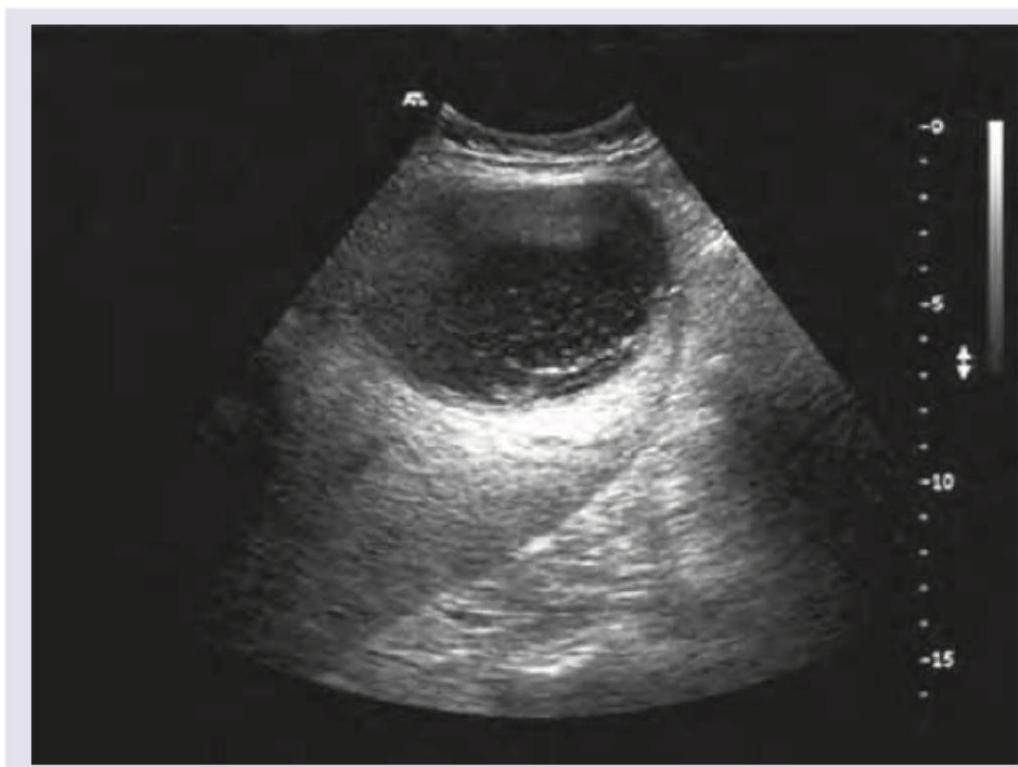

A 28-year-old female patient presents with abdominal pain, fever, night sweats, malaise, and intercostal tenderness. Past history of bloody diarrhea is present. USG liver of the patient is given. Which among the following statements is false?

Explanation: ***Aspiration and culture is the investigation of choice*** - This statement is **FALSE** - while aspiration may be performed, **culture often yields negative results** for *Entamoeba histolytica* as trophozoites are fragile and difficult to culture. - **Serology** (antibody detection), **imaging**, and **response to anti-amoebic therapy** are the preferred diagnostic approaches for amoebic liver abscess. *This condition is caused by an organism that spreads via fecal-oral route* - This statement is **TRUE** - *Entamoeba histolytica* causes amoebic liver abscess and spreads via **fecal-oral route**. - Transmission occurs through ingestion of **contaminated food or water** containing cysts. *Right lobe of the liver is most commonly affected* - This statement is **TRUE** - the **right lobe** is most commonly affected in amoebic liver abscess. - This occurs due to **preferential portal blood flow** and the right lobe's larger size. *Patient may present with pulmonary symptoms* - This statement is **TRUE** - amoebic liver abscesses can cause **pleuropulmonary complications**. - Abscess rupture into the **diaphragm or pleural cavity** can lead to cough, chest pain, and dyspnea.